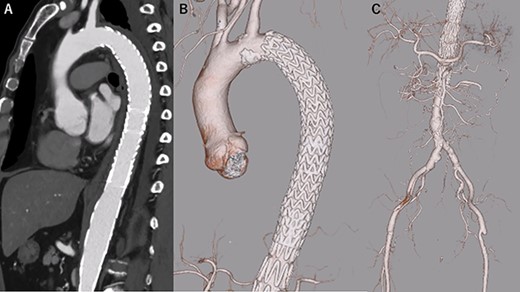

The postoperative course was uneventful, and he was discharged 14 days postoperatively. Rapid aortic remodeling was observed with eCT at 1 and 11 days postoperatively (Fig. 4). Right iliac artery dissection did not impede blood flow and no other complications such as stent-induced new entry (SINE) were observed (Fig. 5). We strictly followed up the false lumen and iliac dissection.

eCT at 11 days postoperatively. (A): Sagittal view, (B, C): 3D reconstruction of the aorta.